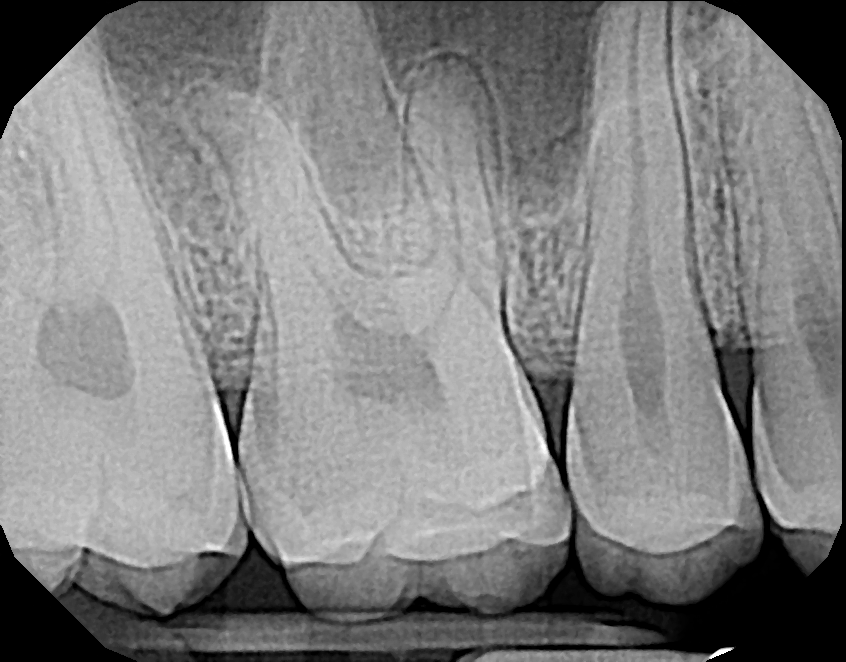

Image Quality

Ultimately, quality is the most important factor in a dental X-ray sensor. A sharp image ensures a proper diagnosis for patients. The Dream Sensor produces easy-to-view, crisp images that work with almost any existing dental software. The results of the direct comparison of DentiMax vs. Dexis are clear.

![]() X-ray taken with the Dexis™ sensor |